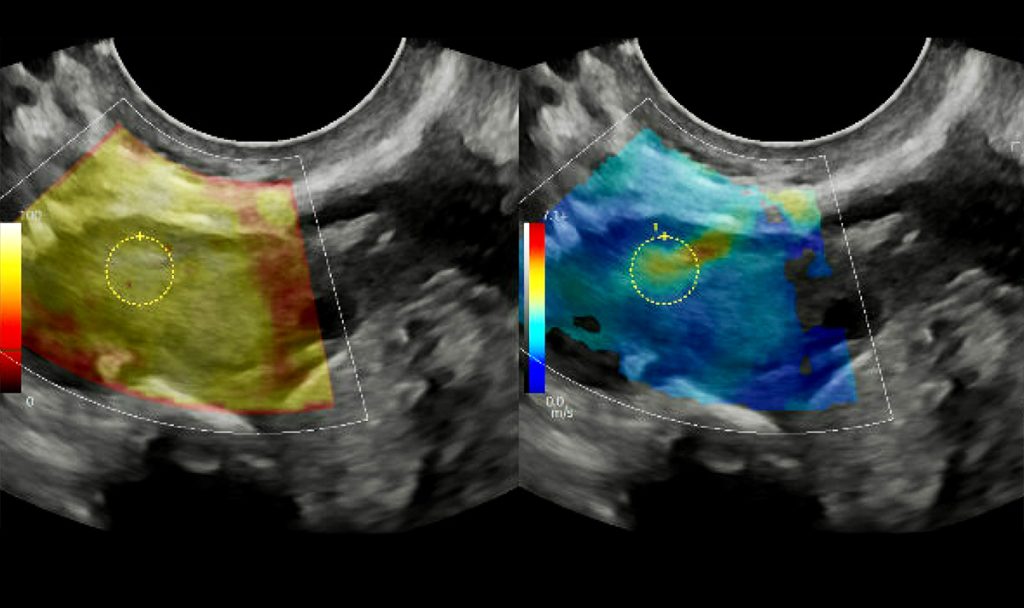

In a study published in GeroScience, researchers led by Francesca Duncan, associate professor of obstetrics and gynecology at Northwestern University Feinberg School of Medicine, explored the potential of Pirfenidone – a drug commonly used to treat pulmonary fibrosis – in reversing ovarian fibrosis in mice. The study demonstrated that reducing scarring in ovaries could extend their functional lifespan, potentially keeping hormone production stable for longer and mitigating the decline in overall health that often accompanies menopause [1].

The study also addresses the broader issue of ovarian fibrosis, which makes the ovaries stiffer as they age – an environment conducive to cancer cell proliferation. By reducing scarring in the ovaries, researchers hope to decrease the risk of ovarian cancer, a disease that often thrives in the collagen-rich environments created by fibrotic tissues. Previous research by Duncan’s team revealed that aged ovaries become excessively inflamed and fibrotic, similar to other tissues in the body that suffer from fibrosis with age [3]. These findings suggest that targeting fibrosis could not only improve ovarian health but also reduce cancer risk.